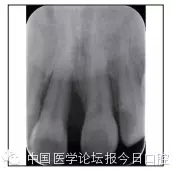

X線檢查

全口曲面體層片(圖3)顯示,患者全牙列牙槽骨吸收;根尖片(圖4)示11近中牙槽骨角形吸收已達(dá)根尖1/3,21牙槽骨嵴頂吸收至根1/2,23牙槽骨近中骨板角形吸收至根1/2。磨牙區(qū)骨嵴頂吸收3mm。治療前頭顱側(cè)位片見(jiàn)圖3,治療前ODS模型見(jiàn)圖5。

圖4 治療前根尖片